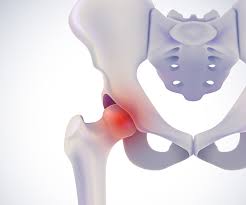

Avascular necrosis, commonly known as AVN, is a condition where reduced blood supply leads to damage of bone tissue, most often affecting the hip joint. Therefore, timely AVN treatment Adilabad is essential to prevent joint collapse and long-term disability. Patients may initially notice pain during movement, which can gradually worsen if left untreated. In Adilabad, structured orthopedic evaluation and planned treatment approaches help patients manage AVN effectively and preserve joint function.

AVN develops when bone tissue does not receive sufficient blood flow. Consequently, the affected bone weakens and may lose its structural integrity over time. AVN treatment Adilabad focuses on slowing disease progression and maintaining joint stability. Moreover, early diagnosis allows for better preservation of natural joint movement. Awareness of symptoms such as persistent hip pain or stiffness plays a key role in timely medical attention.

The hip joint is most commonly affected. Other joints may also be involved in some cases.